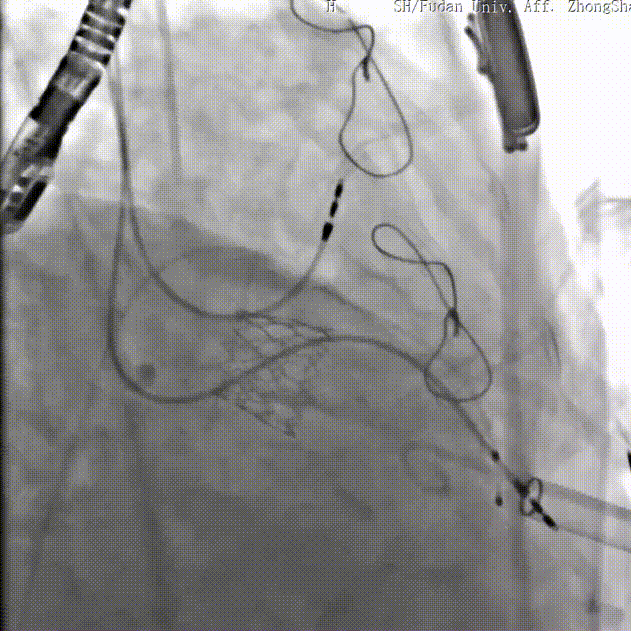

二尖瓣病例:

患者女性,73岁,既往二尖瓣位植入27# Epic猪瓣,超声提示二尖瓣人工瓣膜衰败伴重度关闭不全,瓣叶连枷。该患者还合并重度贫血、低白细胞、低血小板、多囊肝、多囊肾、永久起搏器植入术后、心功能NYHA III级、营养状况极差,术前STS评分12.1%,属于常规外科手术极高风险患者。术前经详尽影像学评估及病例讨论,考虑到患者既往经房间隔切开植入二尖瓣人工瓣膜,房间隔疤痕钙化严重增加穿刺手术风险,决定采用更安全的经心尖途径植入27号Renato球扩式瓣中瓣。

手术耗时约1小时,全程生命体征平稳,几乎无出血。瓣中瓣植入位置理想,功能表现出色:左房压自术前50/15/27mmHg降至21/11/15mmHg,二尖瓣平均流速自2.2m/s降至1.4m/s,二尖瓣平均跨瓣压差自6mmHg降至3mmHg。

▲球扩二尖瓣 ▲左室造影